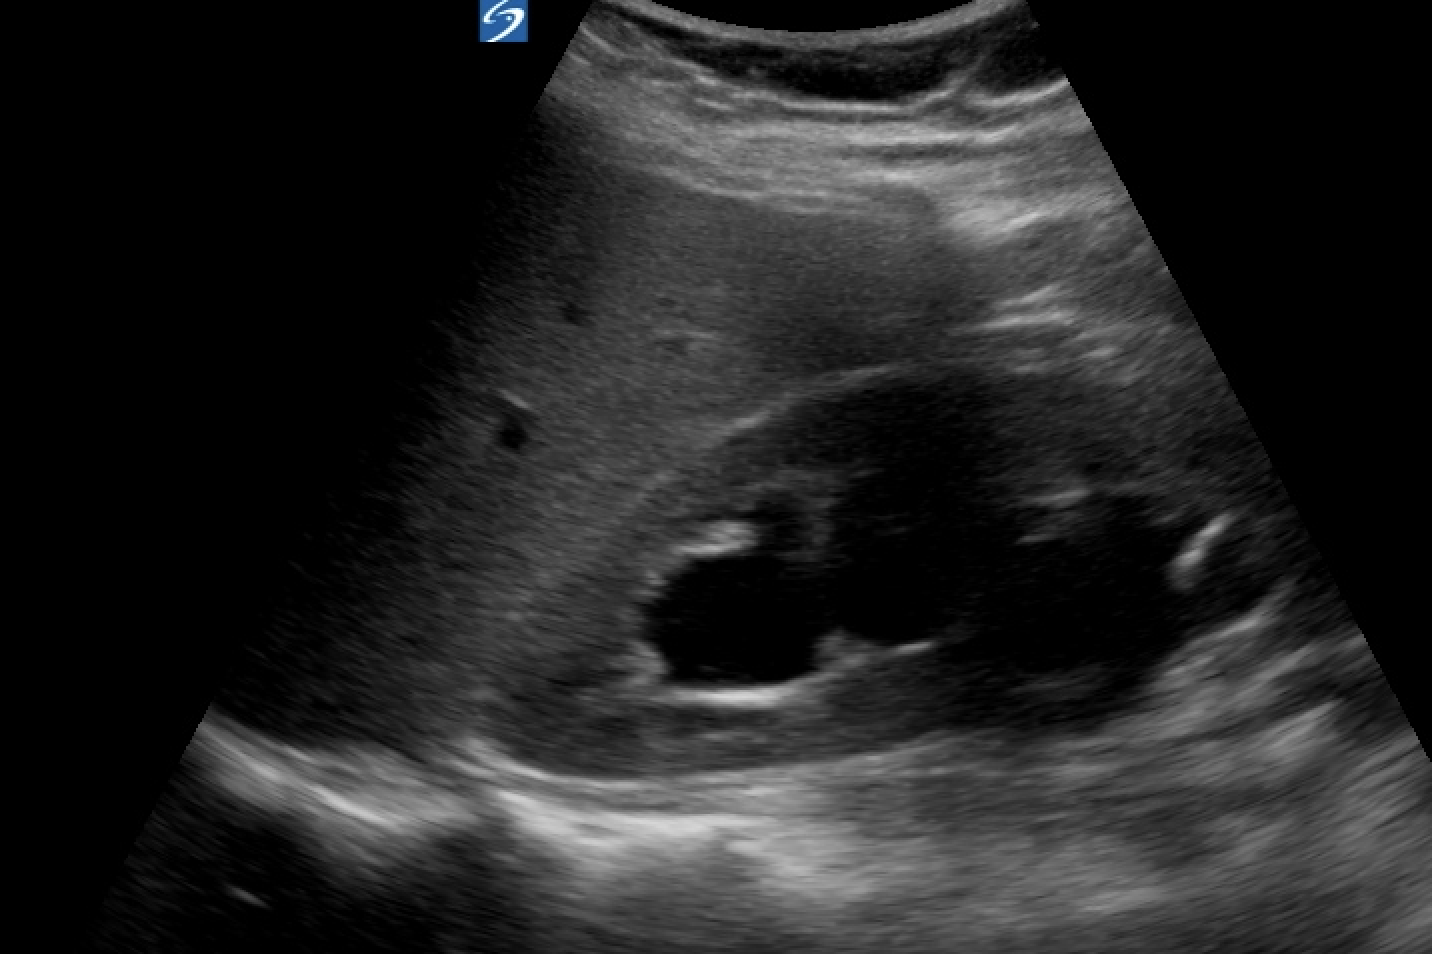

EDUS revealed this bilaterally:

Interestingly, I couldn't see a dilated ureter at the pelvis. Also there was no ureteric dilatation at the VUJ and her ureteric jets were normal. Her bladder post void volume was small excluding an outlet obstruction. Aorta and retroperitoneum was NAD.

If you look closely at her US images, you can see that her cortex is normal thickness bilateral despite quite significant "hydronephrosis". Also on the left, the anechoic areas seem discrete and round.